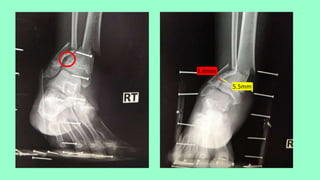

• Close transverse fracture right distal tibia with minimal displacement

• Close multifragmentary fracture right distal fibula with displacement

Syndesmotic injury

5.5mm

3.4mm